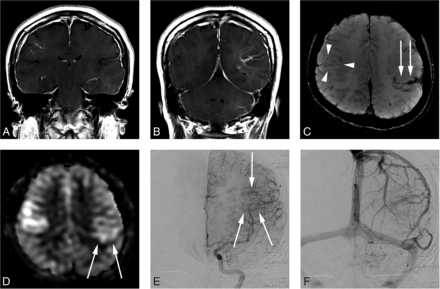

A 34-year-old woman presenting with a headache (case 6). A and B, Contrast-enhanced T1-weighted coronal MR imaging shows a DVA-like lesion in the bilateral parietal lobes. C, SWI demonstrates only hypointense signal in both the right (arrowheads) and left (arrow) lesions. D, The ASL quantitative CBF image demonstrates mildly hyperintense signal intensity in the parenchyma, corresponding to the location of the lesion. The left-sided lesion exhibits particularly subtle signal (arrows). E, In the late arterial phase of DSA, dilated medullary veins are gradually and subtly visualized (arrows). F, In the venous phase, dilated medullary veins draining to a collecting vein typical of a DVA are seen.